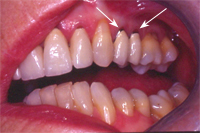

Ein 31 Jahre alter Patient zeigt einen starke Zahnfleisch-Rückgang im Oberkiefer (Abb. 1 und 3) und wir beschliessen, diese Rezessionen zu behandeln.

Der Erfolg der Behandlung ist deutlich in den Abb. 2 und 4 zu sehen. Sehr augenfällig konnte die Situation um den Eckzahn im linken Oberkiefer verbessert werden (vergleiche dazu Abb. 3 vorher und Abb. 4 nachher).